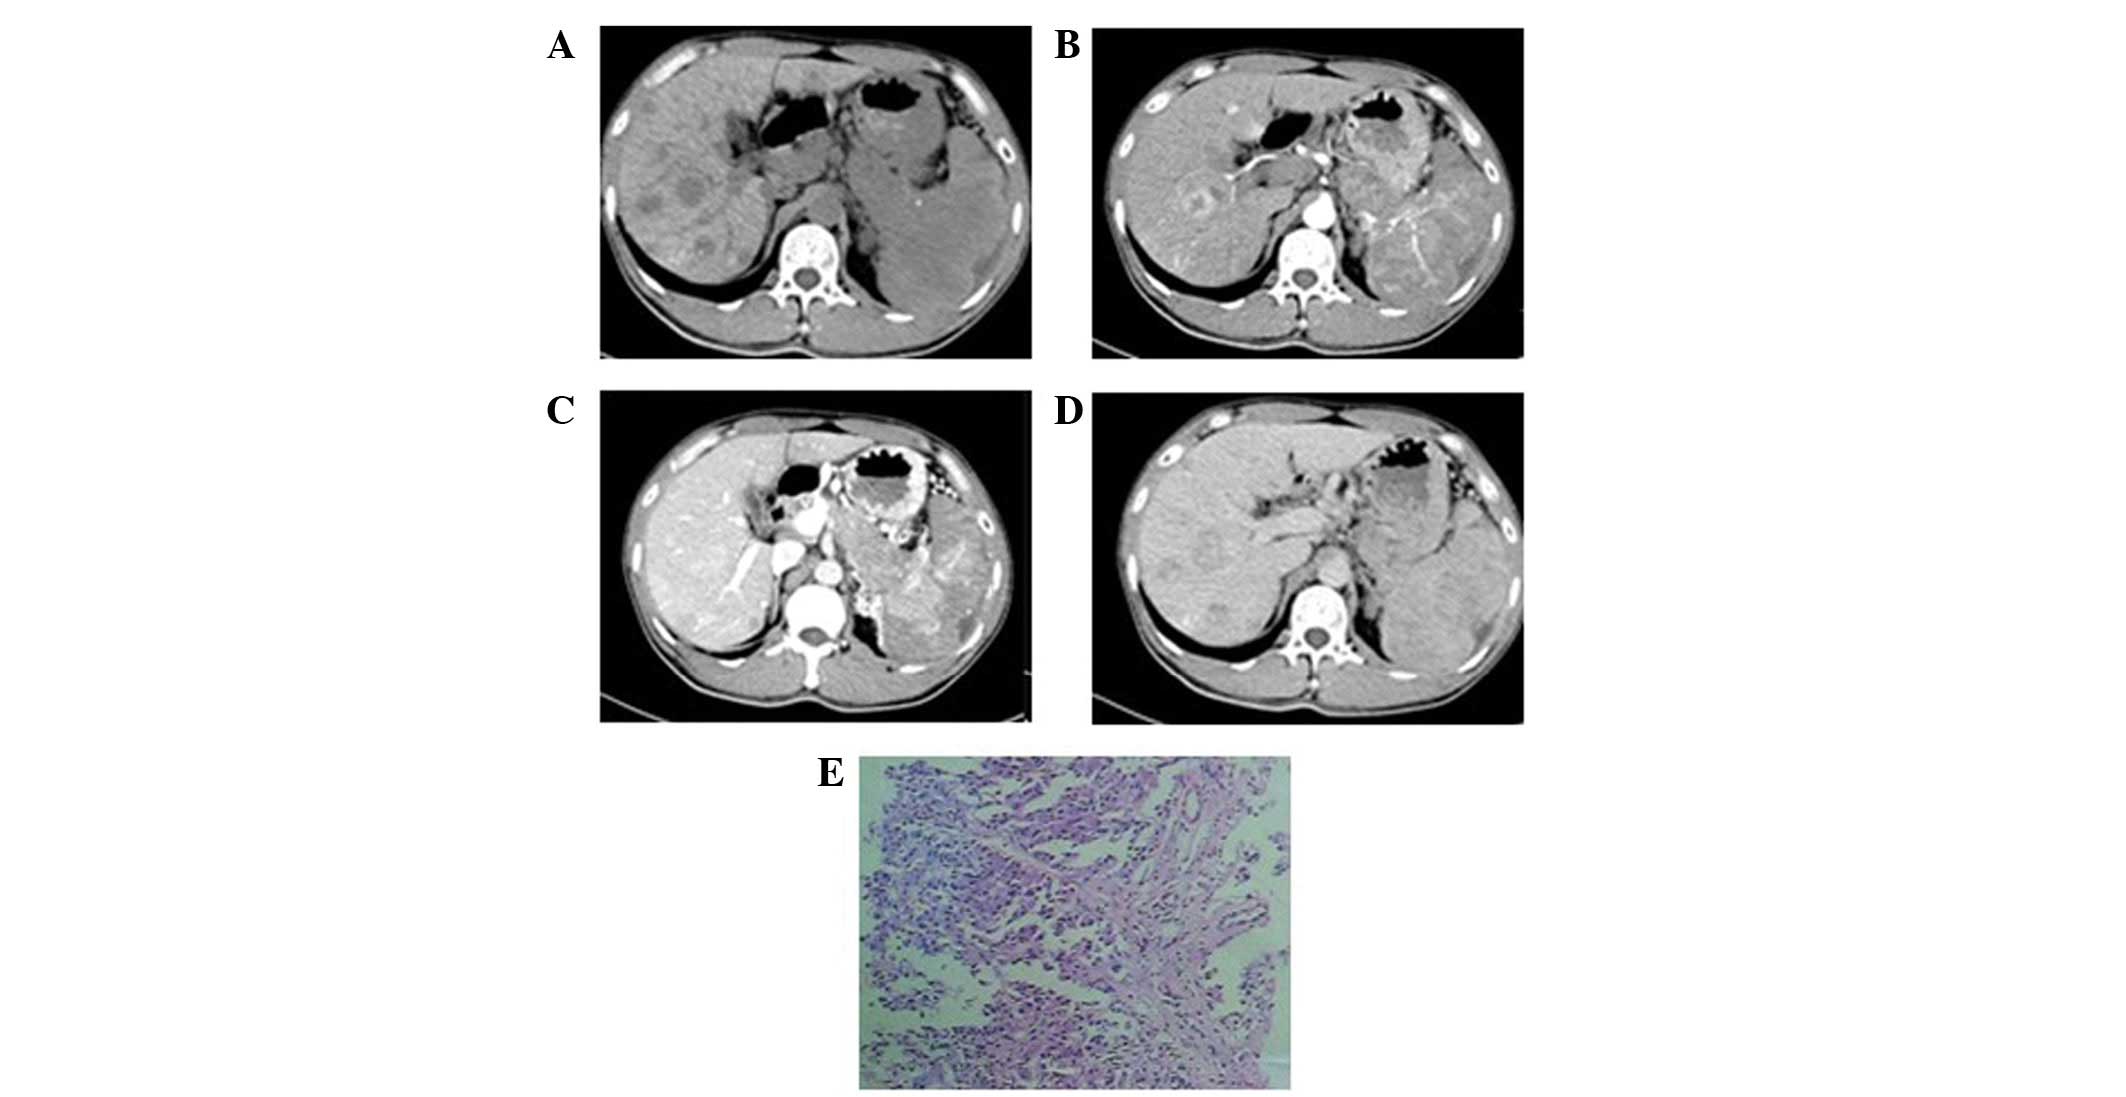

In the eight patients exhibiting multiple intrahepatic lumps, the foci were of various sizes. In four patients, the diameters of the largest foci were >7 cm whilst in the remaining four, the diameters were <2 cm. Plain CT scan showed low-density lesions. The four cases with larger masses had a lower density liquefied necrotic area (Figs. 2A, 3A and 4A) while the four cases with smaller foci had a relatively uniform density (Fig. 5A). The boundaries of the foci were unclear in six patients (Figs. 3 and 5), while they were clear in the other two cases (Fig. 2). All foci showed uneven enhancement in the arterial phase, six of which exhibited annular enhancement (Figs. 2B–4B). In six patients, the degree of enhancement was found to decline in the portal venous phase (Figs. 2C, 3C and 4C) and the delayed phase (Figs. 2D, 3D and 4D). In two patients, the enhanced area was enlarged in the portal venous phase (Fig. 5C) and the enhancement extended over a long period of time. The degree of enhancement in the delayed phase (Fig. 5D) declined in all cases, and the density of the foci was generally uniform. In one patient (Fig. 6), the foci were not observed in plain scanning but were clearly observed in the arterial phase and absent in the portal venous and delayed phases.

Figure 4

Poorly differentiated neuroendocrine carcinoma in a 46-year-old female. (A) Precontrast computed tomography showed multiple lumps of various sizes in the right and left hepatic lobes with obscure boundaries, uniform density and a maximum diameter of 10 cm. (B) In enhancement scanning, obvious enhancement was observed in the arterial phase and an annular enhancement was identified in the largest mass. (C and D) The enhancement was observed to decline in the portal venous and delayed phases, respectively. (E and F) Hematoxylin-eosin staining (magnification, ×200 and 100, respectively) revealed the poorly differentiated cancer cells to be smaller, with less cytoplasm, angular and trachychromatic nuclei and karyokinesis.